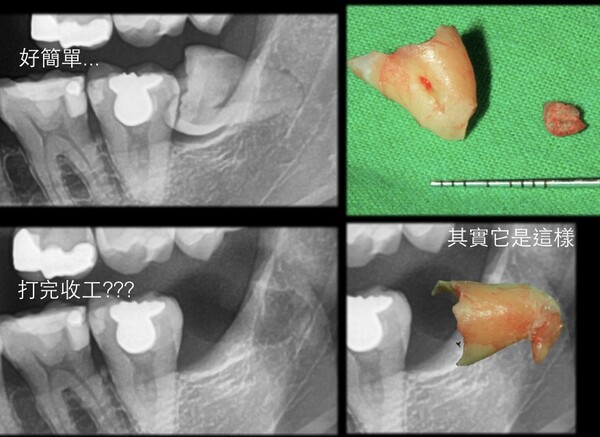

微創智齒手術案例分享

成效因人而異,必須跟從專業醫師指引

案例照片與內容均取得當事人授權同意使用,請勿私自轉載與分享